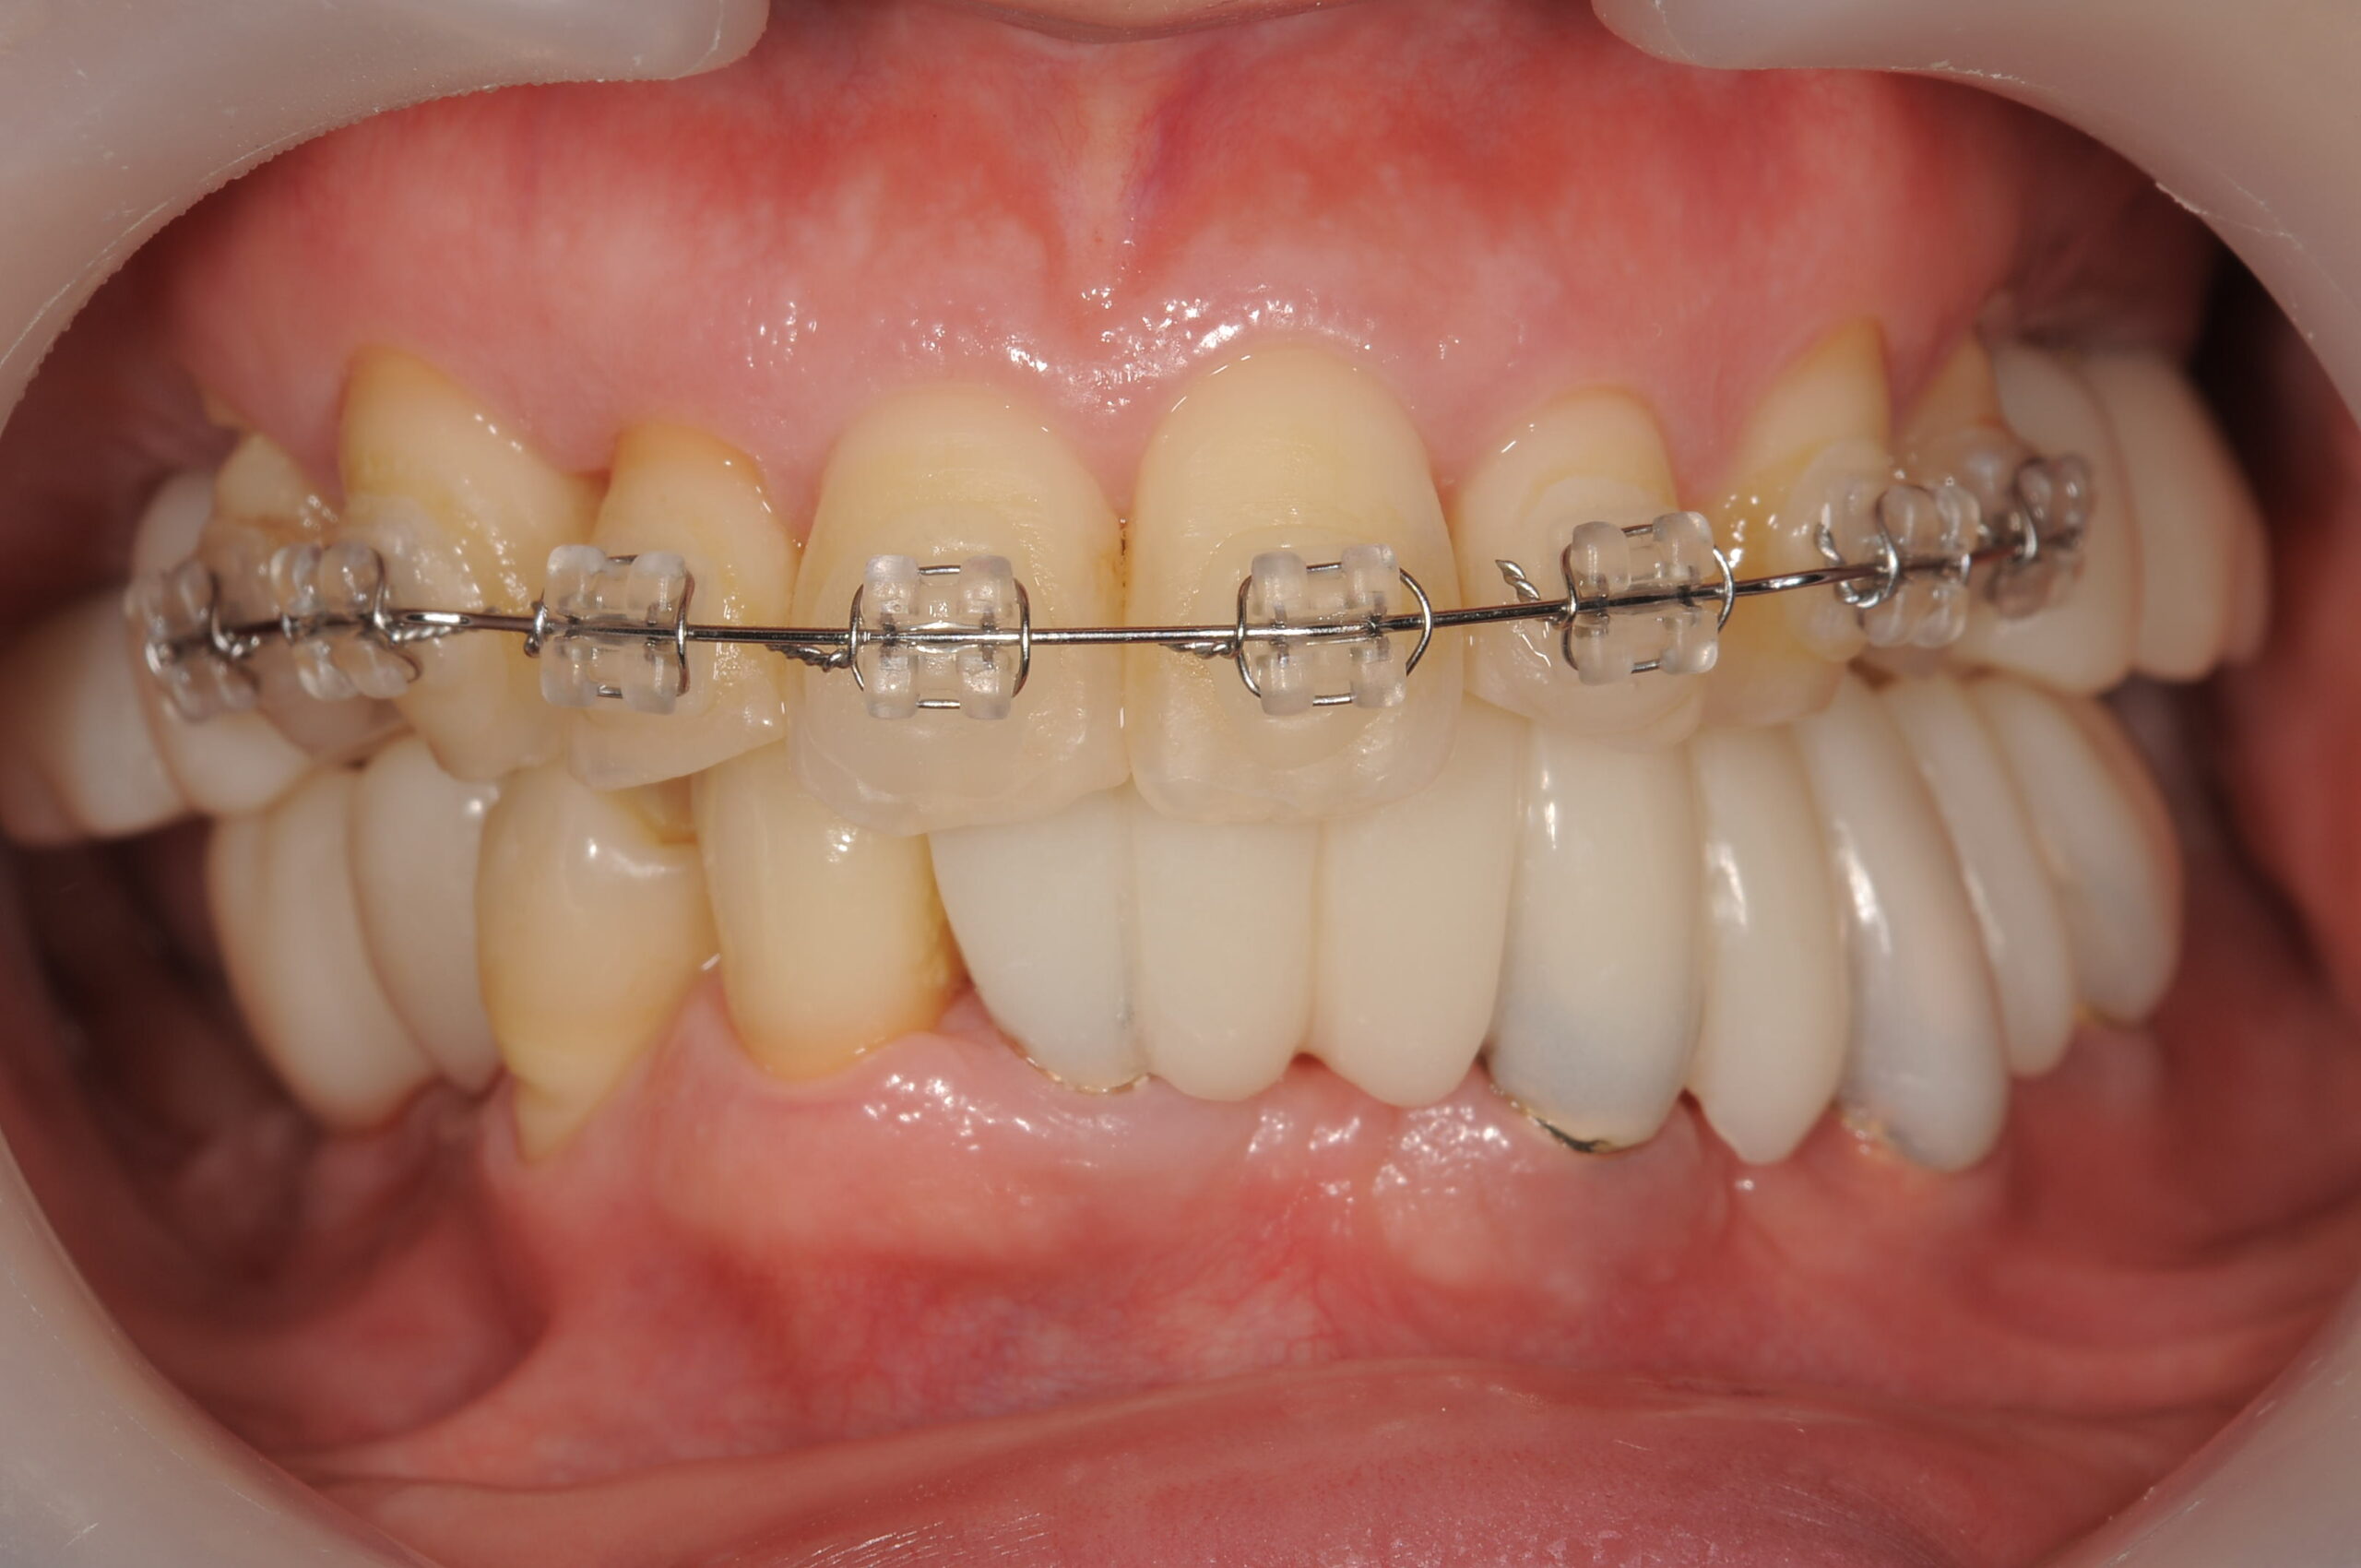

下あごにと上顎の両側にインプラントの仮歯が入り、歯列矯正により歯並びもよくなりました。